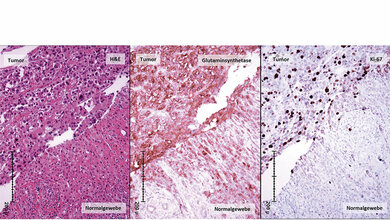

Im Mausmodell hat das Forschungsteam den Signalweg zwischen P2Y14-Liganden und -Rezeptor überprüft. Eine vermehrte Freisetzung dieser aktivierten Zuckermoleküle führte zur Aktivierung der Sternzellen. Eine Inaktivierung des P2Y14-Rezeptors verringerte dagegen die Fibrosebildung. „Auch in menschlichen hepatischen Sternzellen konnten wir den P2Y14-Rezeptor mit Hilfe spezieller Antikörper nachweisen“, sagt der Hepatologe. Der Zusammenhang zwischen dem Zelltod des Lebergewebes und der Fibrosebildung habe sich auch in Untersuchungen gesunder und kranker menschlicher Leber bestätigt. Die Entdeckung könnte ein wichtiger Schritt zu einer antifibrotischen Therapie sein. Als nächstes müsste dafür ein Antagonist gefunden werden, der den P2Y14-Rezeptor blockieren und darüber die Entstehung von Leberfibrose vermindern kann.